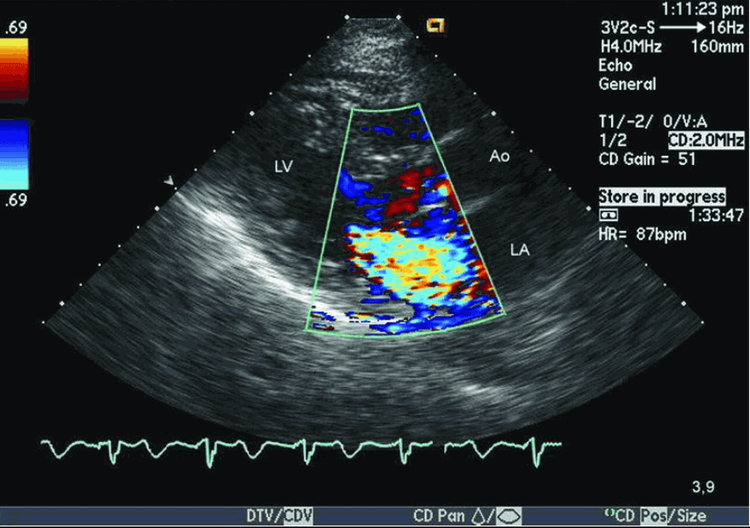

Siêu âm tim Doppler màu là phương tiện chẩn đoán hình ảnh hiện đại rất có giá trị trong chẩn đoán các bệnh lý tim mạch, đặc biệt các bệnh lý van tim. Khảo sát van hai lá có ý nghĩa trong việc đánh giá mức độ và lựa chọn phương pháp điều trị.

Siêu âm Doppler màu là hình thức siêu âm hiện đại có độ chính xác cao nhất và hình ảnh siêu âm có màu dễ quan sát. Đây là phương pháp thăm dò chẩn đoán hình ảnh nhằm mục đích đánh giá trạng thái hoạt động, cấu trúc của tim hay các tình trạng chuyển dịch của máu trong hệ tuần hoàn, trạng thái huyết động. Từ đó, phát hiện các dấu hiệu hoặc các bệnh lý bất thường của tại hệ thống tim mạch. Do đó, đây là phương pháp được các bác sĩ chỉ định và sử dụng nhiều trong quá trình chẩn đoán và đánh giá bệnh lý tim mạch. Ngoài ra, siêu âm Doppler màu còn chỉ định trong 1 số bệnh lý khác.

Để chẩn đoán chính xác hẹp van hai lá và mức độ hẹp để có thái độ xử trí kịp thời cần thực hiện siêu âm Doppler màu.

3. Đánh giá hẹp van hai lá trên siêu âm tim Doppler màu

Mục tiêu của siêu âm tim Doppler màu trong hẹp van hai lá:

- Chẩn đoán xác định và chẩn đoán mức độ hẹp van hai lá,

- Tính chất lá van, vòng van, bờ mép van và bộ máy dưới van

- Diện tích mở van

- Kích thước buồng tim và dòng máu quẩn trong hay cục máu đông nhĩ trái

- Áp lực động mạch phổi

- Kích thước, chức năng thất trái

- Tổn thương các van tim khác, bệnh tim khác phối hợp

- Siêu âm Doppler màu giúp đánh giá vận tốc đỉnh dòng chảy qua van hai lá > 1m/giây gợi ý có hẹp van hai lá, song dấu hiệu này không đặc hiệu, có thể xảy ra do nhịp nhanh, tăng co bóp, hở hai lá và thông liên thất

- Đo được chênh áp qua van hai lá (đo viền phổ dòng chảy qua van hai lá) cho phép ước lượng mức độ nặng của hẹp van.

- Cho phép đánh giá tổn thương thực tổn kèm theo như hở van hai lá, hở chủ và mức độ, điều này rất quan trọng giúp cho quyết định lựa chọn phương pháp can thiệp van hai lá thích hợp.

- Siêu âm Doppler tim dùng để đánh giá diện tích lỗ van hai lá khá chính xác, từ đó xác định và đánh giá mức độ hẹp.